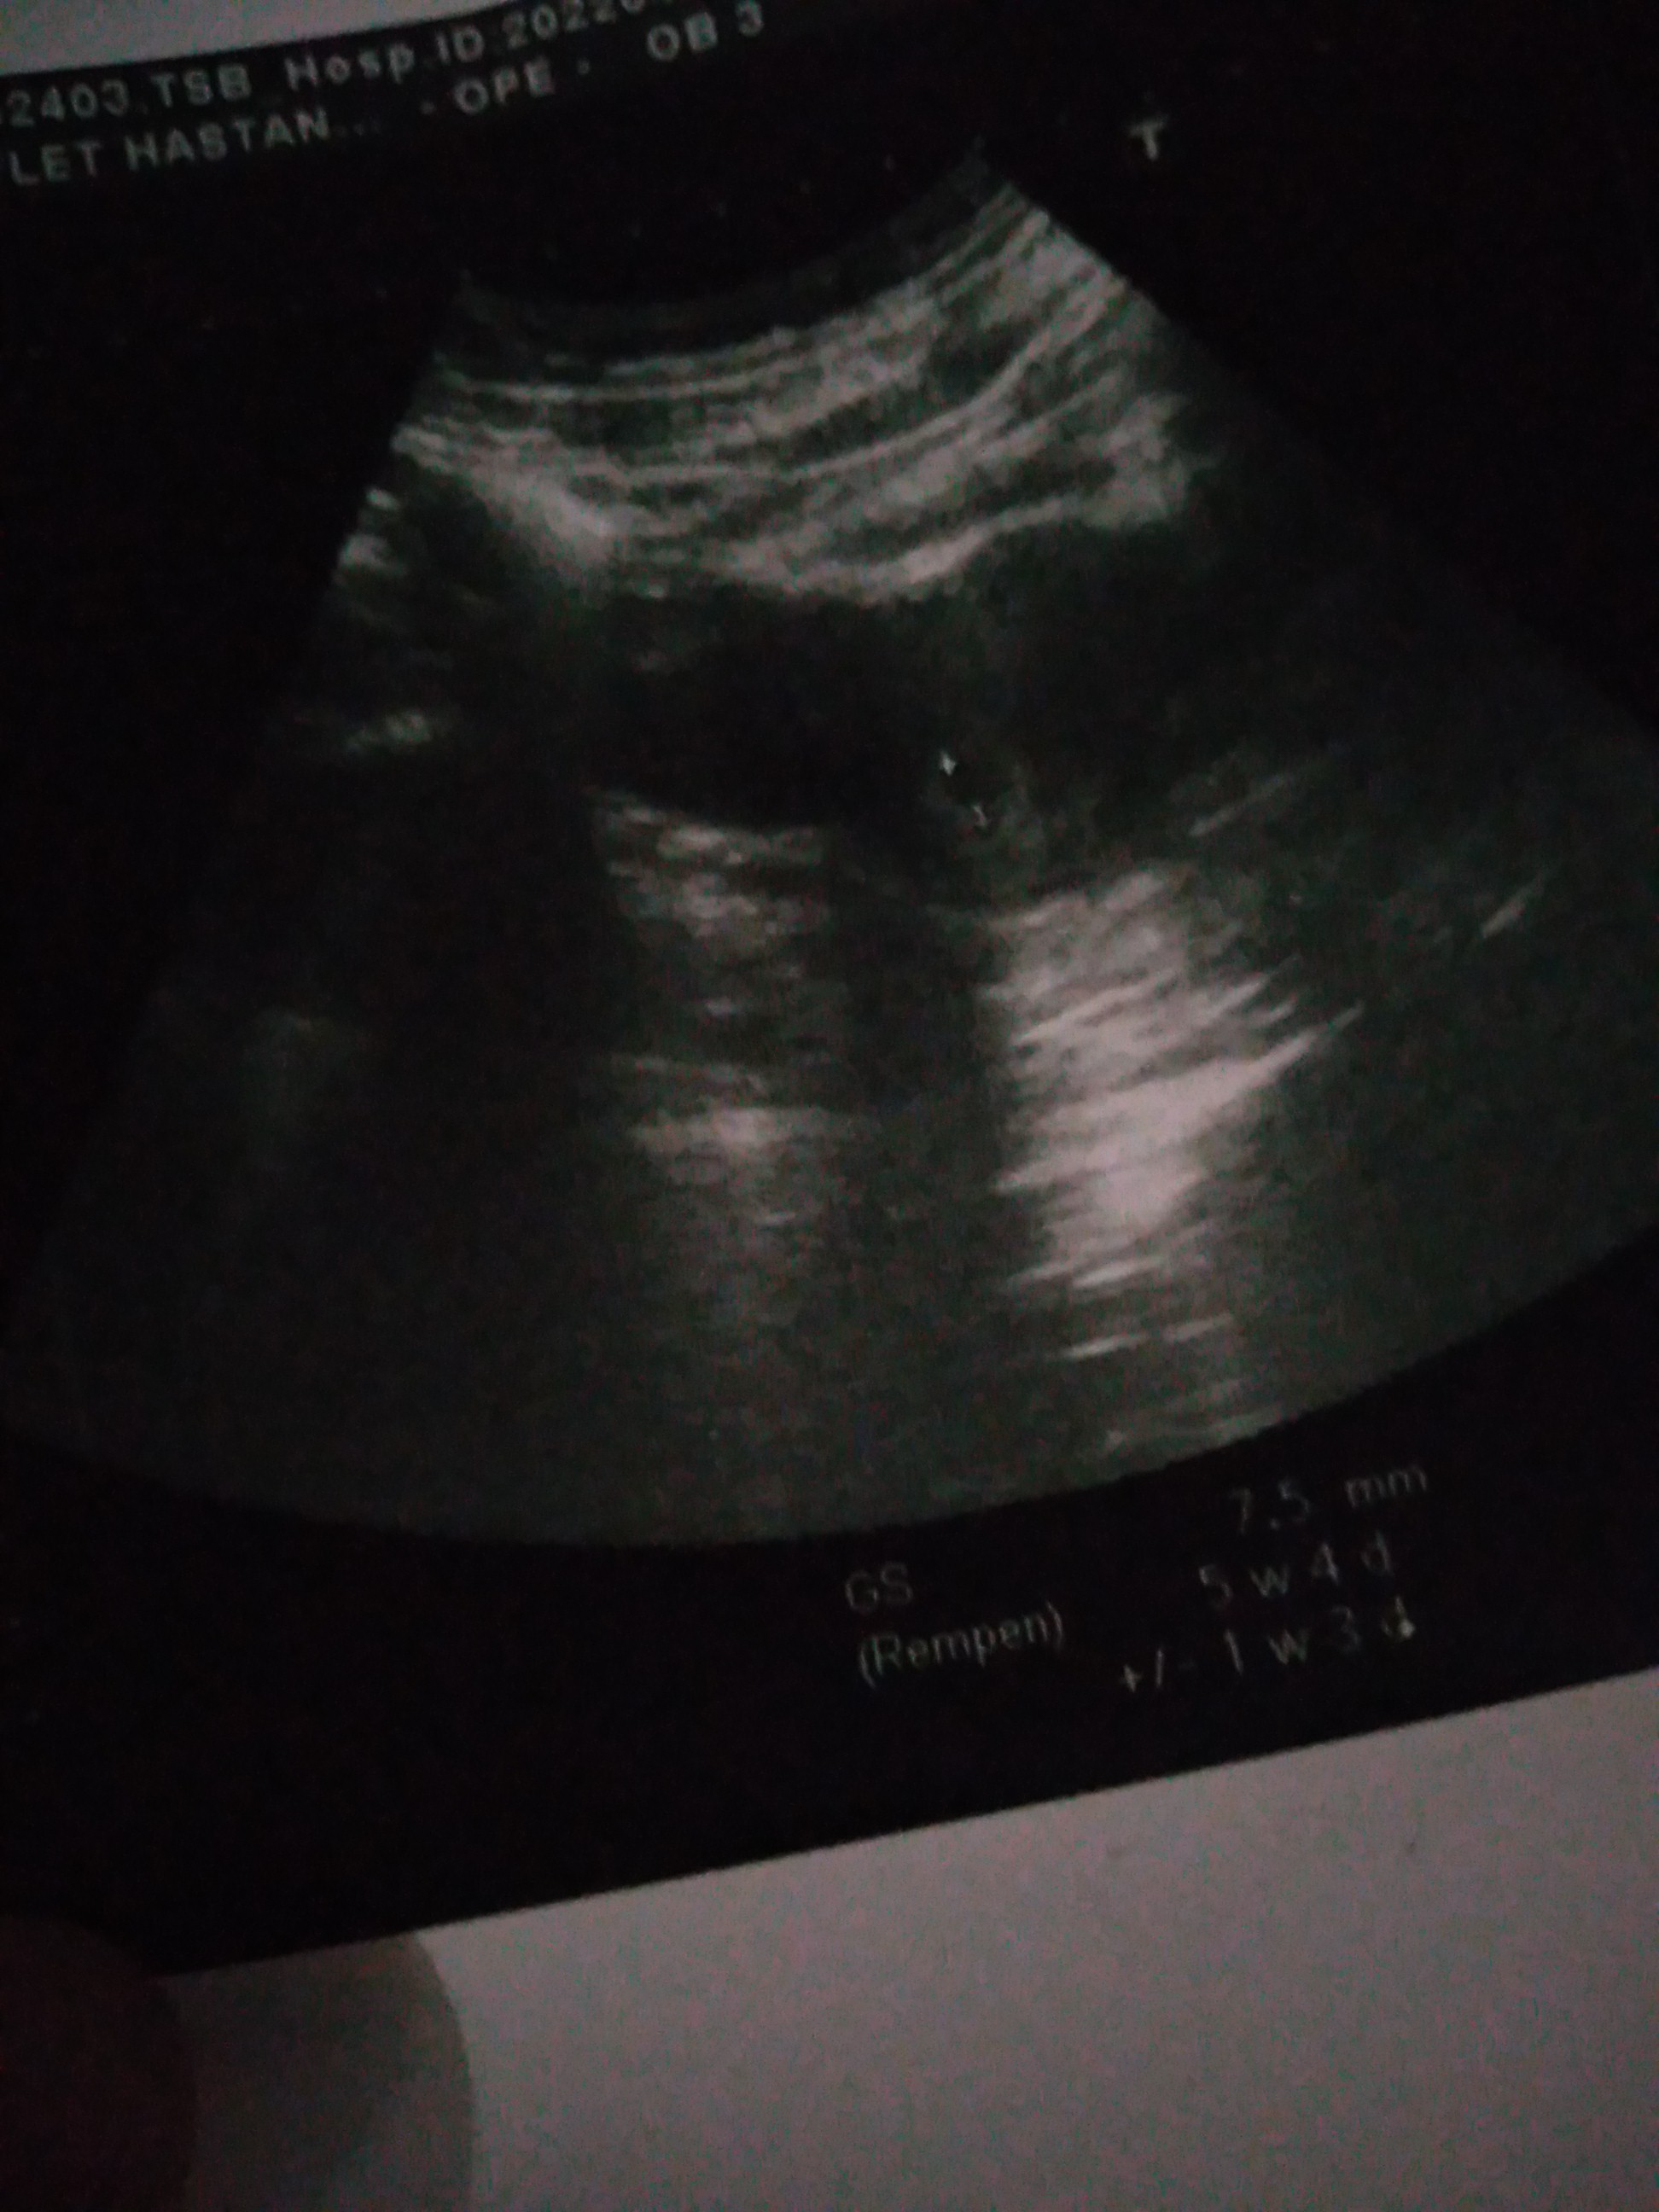

İnsanllah cnm herşey gönlünce olur Allah inşallah saglikla kucağına almayi nasip eder benmde ultrasyon resmin şöyle 5+4 haftayken normal mi

Alta bir ok var orda beyaz birşey var oda yuvarlak gibi o nedir bilmiyorum bile doktor bilgilendirmedi devlet olduğu için 7 haftalık oraya gidicm tekrardan daha gitmiycm oraya yolk kesesi mi acaba o

Evet göbekten baktrdm cnm yuvarlak olan varya o artı konulmuş 4+6 gitmiştim 5+4 haftalık olduğumu öğrenmistm orda